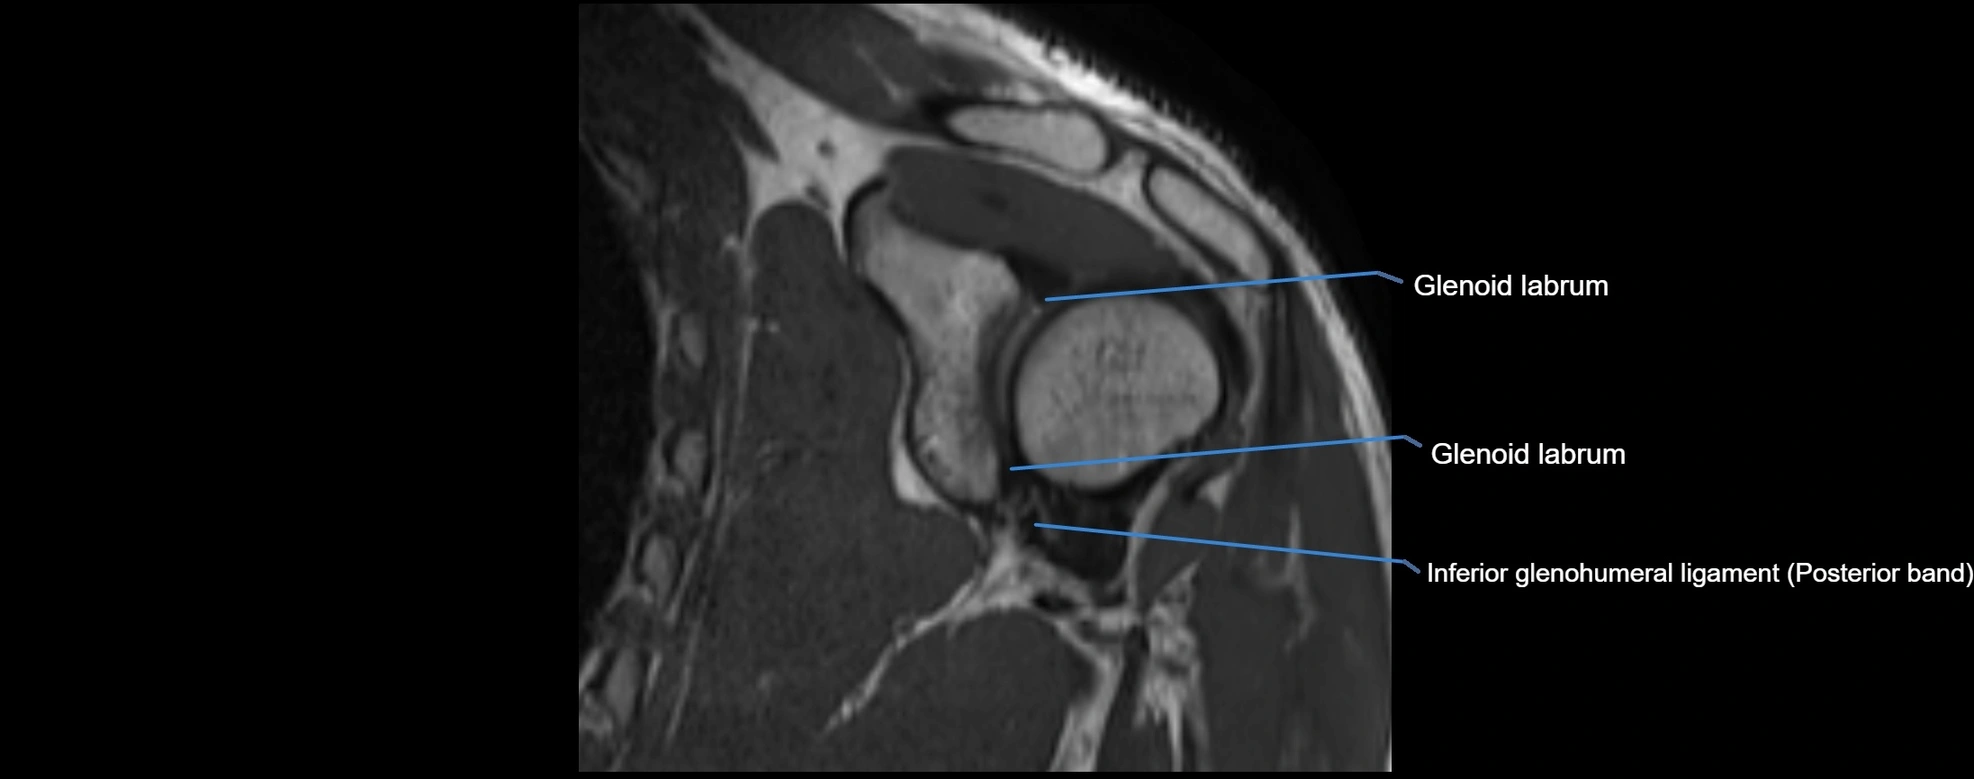

MRI images

image